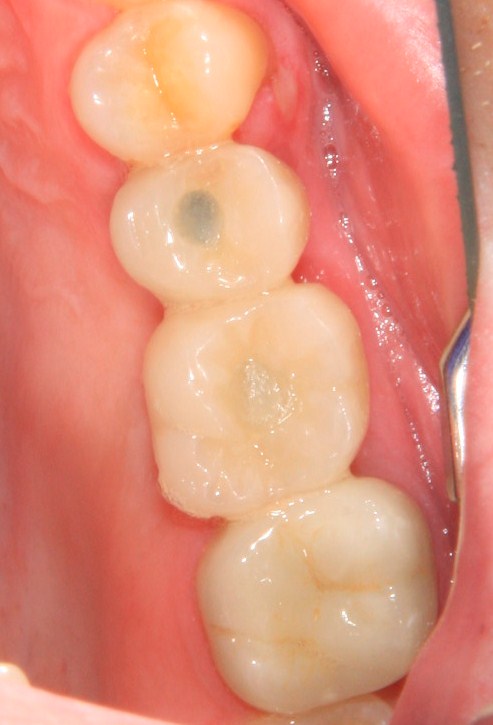

Немедленная имплантация — оптимальное решение в любой клинической ситуации